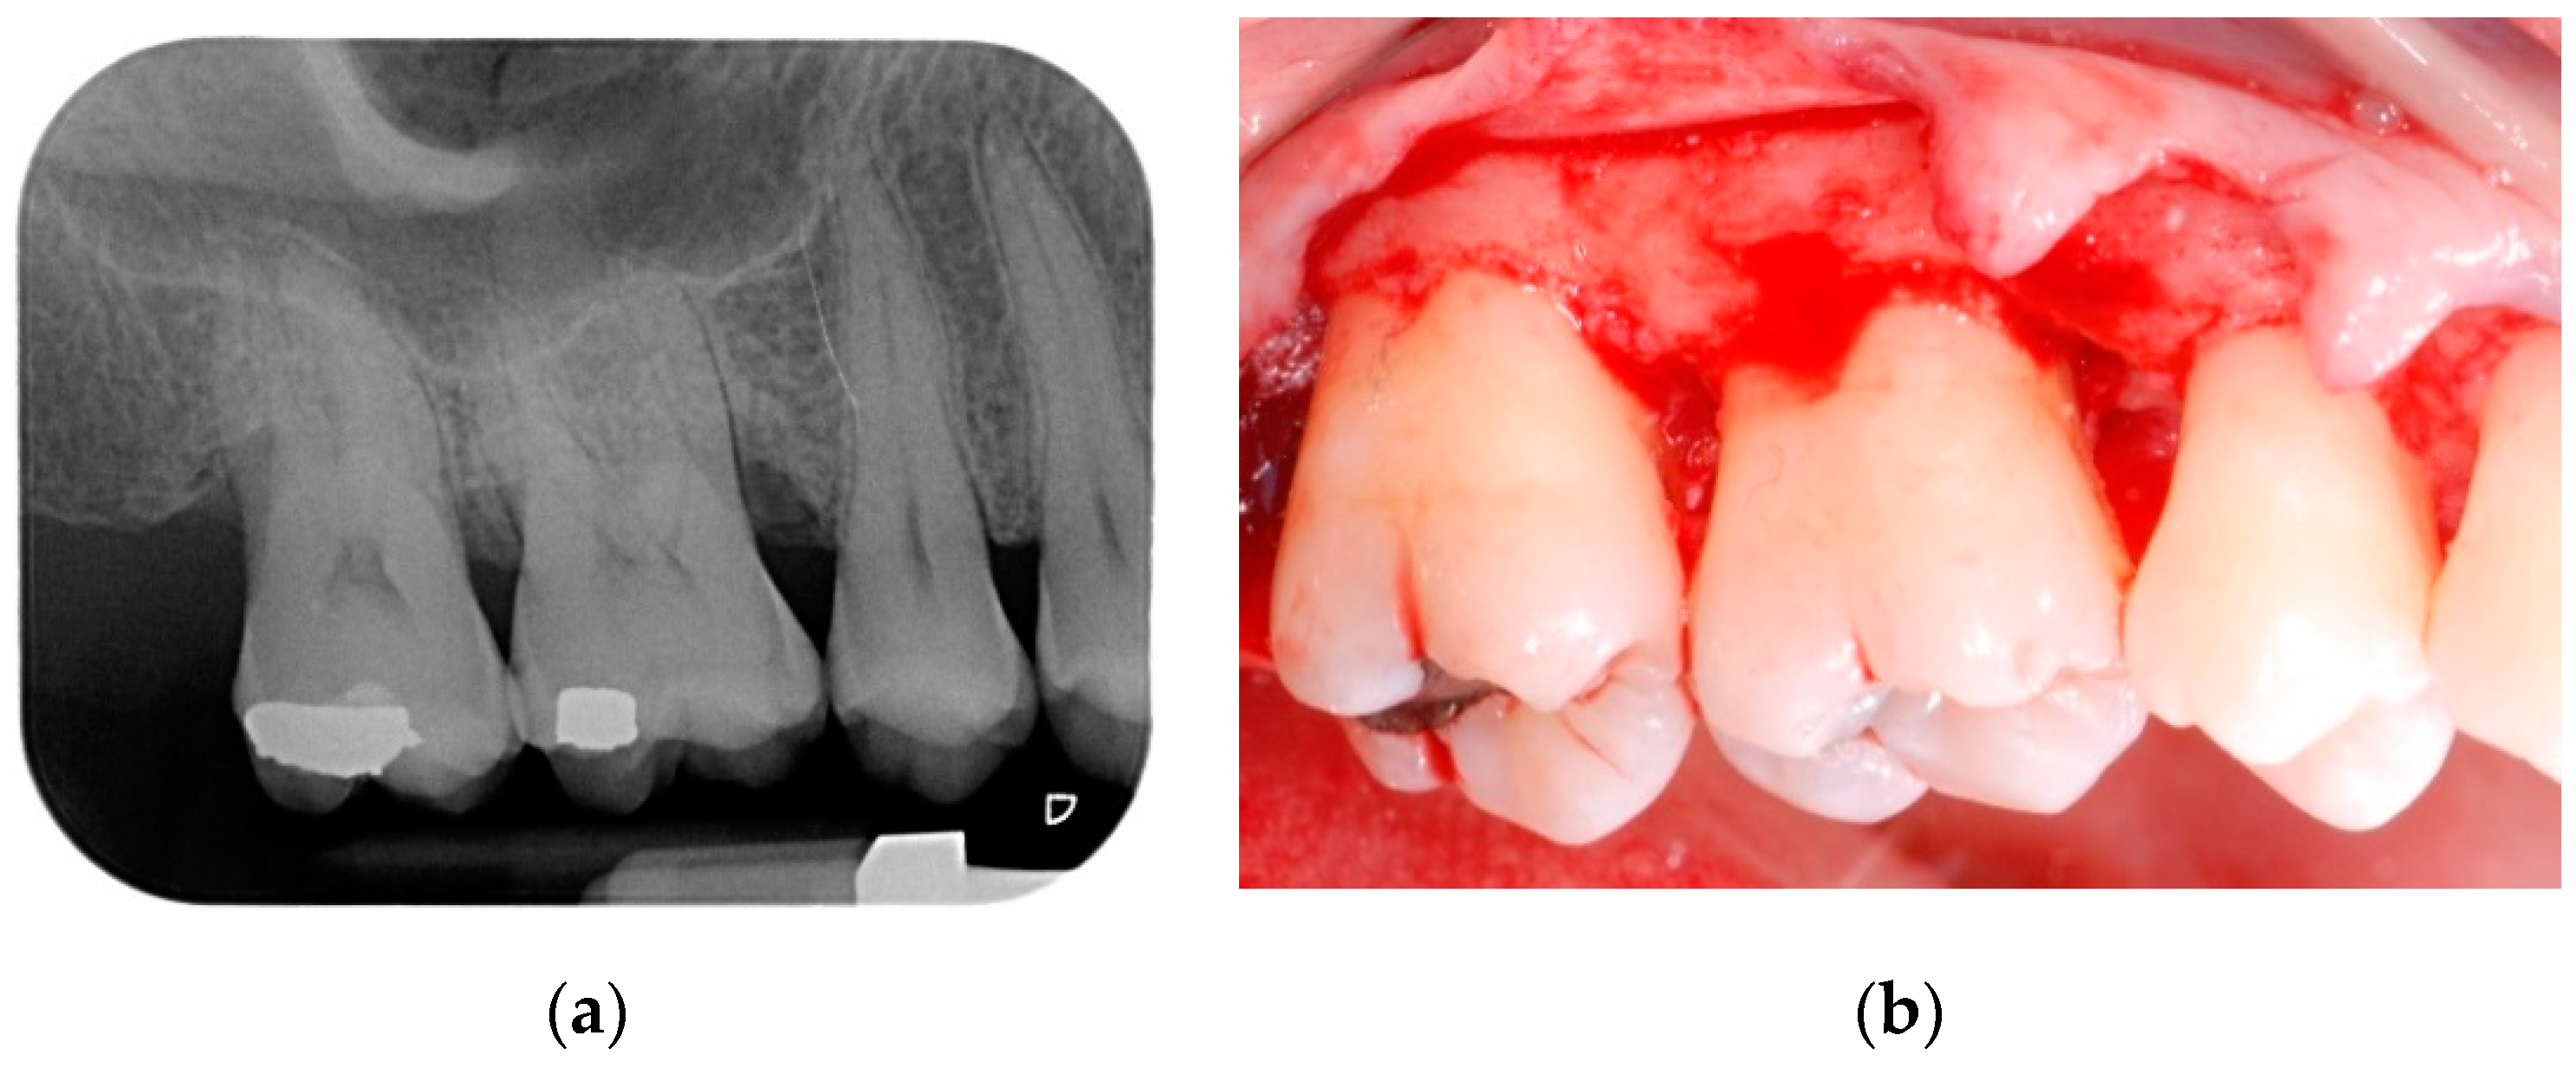

All patients were treated under local anesthesia (articaine 4% with adrenaline 1:100,000). Incisions were performed with a 15b and/or 15c scalpel blade and papillae were preserved in the areas to be regenerated following a previously described technique [25]. Incisions were extended to the adjacent teeth in case multiple sites had to be treated. A full thickness flap was elevated in order to get access to the root and the periodontal intrabony defect (Figure 1a,b); a combination of ultrasonic device and manual curettes was used to debride the area and to remove calculus and inflammatory tissue. The intrabony component of the defect was then filled by a composite graft consisting of nanohydroxyapatite powder (NHA) with crystals varying in size between 70 and 100 nm (Neo Active Apatite, Ghimas, Casalecchio di Reno, Italy) mixed with poly lactic-co-glycolic acid (PLGA) (Fisiograft Gel, Ghimas, Casalecchio di Reno, Italy) (Figure 2a). The mix ratio was 1:1 by volume. The buccal flap was then slightly released by longitudinal periosteal incision and 5.0 monofilament sutures were used to obtain primary soft tissue closure with vertical mattress sutures (Figure 2b).

Figure 1.

(a) Pre-operative periapical radiograph; (b) A full thickness flap was elevated in order to get access to the root and the periodontal intrabony defect.